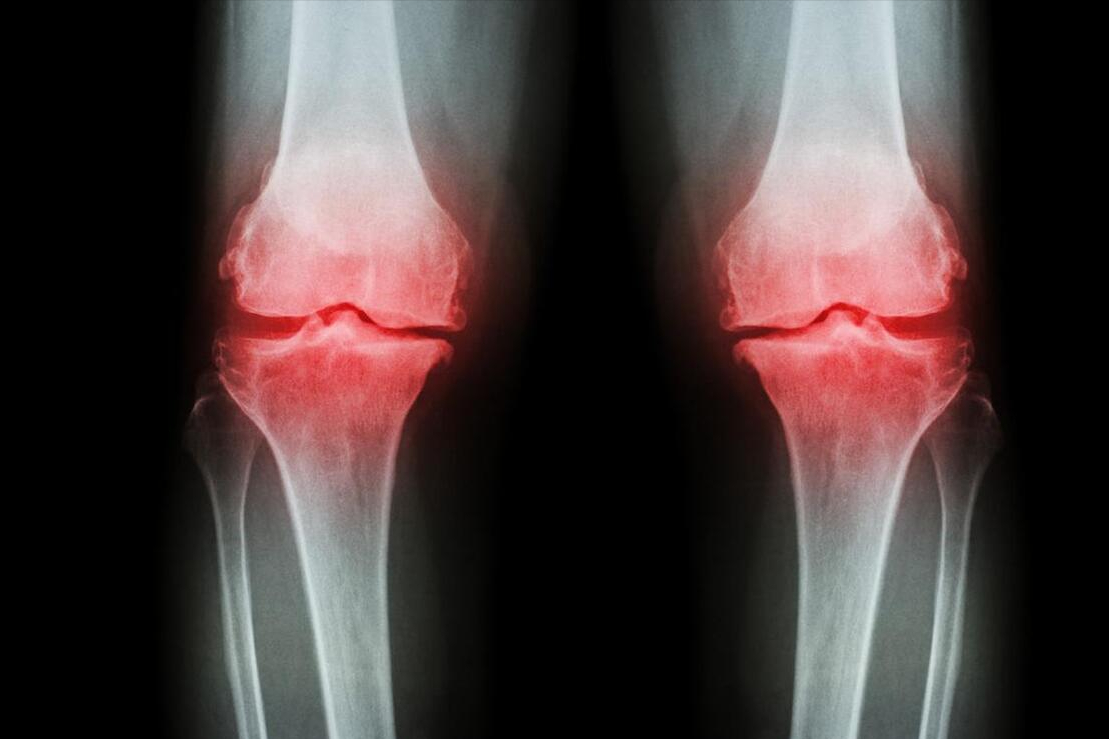

缺硒直接导致的两种疾病就是克山病和大骨节病。大骨节病通常发生于青少年中的一种骨关节系统病。症状表现为关节骨变粗、变形,运动时疼痛,肌肉萎缩,严重时甚至丧失劳动能力。我国医疗人员曾在该病的流行区内使用亚硒酸钠片和维生素E进行试验治疗,收到了较好的反馈。

确诊克山病后,患者可表现为脸色苍白、头晕头痛、呼吸急促、恶心以及急性心肌损害。并且该疾病发作极为迅速,较大一部分患者未得到及时的救治危及性命。由于硒在谷胱甘肽过氧化物酶和辅酶Q中是主要构成成分,并且这两种酶分别具有保护细胞膜和维持心脏生理功能的作用,于是,硒成为治疗克山病的主要治疗药物。